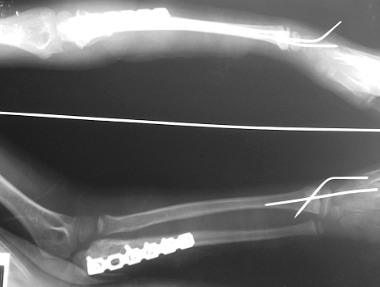

手术:完善各项检查无手术禁忌证后,在臂丛神经阻滞麻醉下,首先切开复位、钢板内固定尺骨骨折,然后手法闭合整复桡骨小头脱位、盖氏骨折,经皮克氏针内固定桡骨远端骨折,避免损伤桡骨远端骨骺;最后行前臂小夹板外固定。术后拍摄X线片(图3),常规预防感染,中药三期辨证施治,指导患肢进行功能训练。术后6周拆除克氏针及小夹板,7个月时取出内固定,前臂旋转、肘腕关节功能均恢复正常。

图3 术后X线片